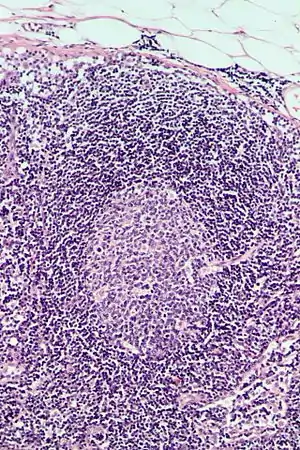

Follicular hyperplasia (FH) is a type of lymphoid hyperplasia and is classified as a lymphadenopathy, which means a disease of the lymph nodes. It is caused by a stimulation of the B cell compartment and by abnormal cell growth of secondary follicles. This typically occurs in the cortex without disrupting the lymph node capsule.[1] The follicles are pathologically polymorphous, are often contrasting and varying in size and shape.[2] Follicular hyperplasia is distinguished from follicular lymphoma in its polyclonality and lack of bcl-2 protein expression, whereas follicular lymphoma is monoclonal, and expresses bcl-2.[3]

Follicular hyperplasia can be distinguished among other diseases by observing the density of a lymph follicle on low magnification. Lymph nodes with reactive follicles contain extensions outside its capsule, follicles present throughout the entire node, obvious centroblasts and the absence or diminishing mantle zones. Immunohistochemistry can help distinguish a difference between a patient with follicular lymphoma to follicular hyperplasia.[1] Reactive follicular hyperplasia does not express BCL2 proteins in B cell germinal centers and are absent light chain reaction in immunostaining and flow cytometry as well as absent IG rearrangements.[1]

BCL2 protein expression is usually absent in follicular hyperplasia but prominent in follicular lymphomas. A comparison with other stains that include germinal center markers such as BCL-6 or CD10 is useful to compare when determining a proper diagnosis.[1] CD10 positive cells are metalloproteinase which activate or deactivate peptides through proteolytic cleavage.[9]